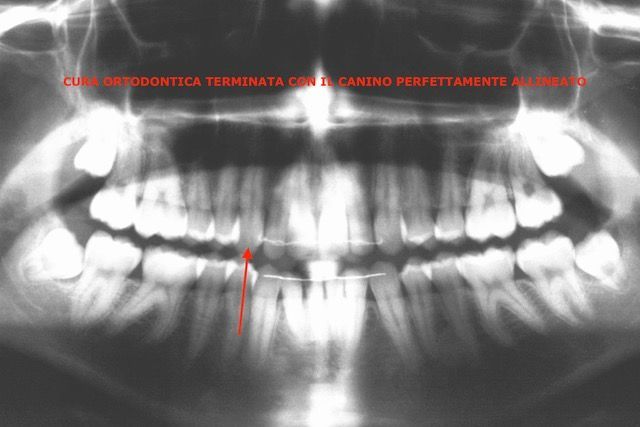

Cura ortodontica terminata con i canini perfettamente allineati

Canino incluso

Posizione orizzontale del canino